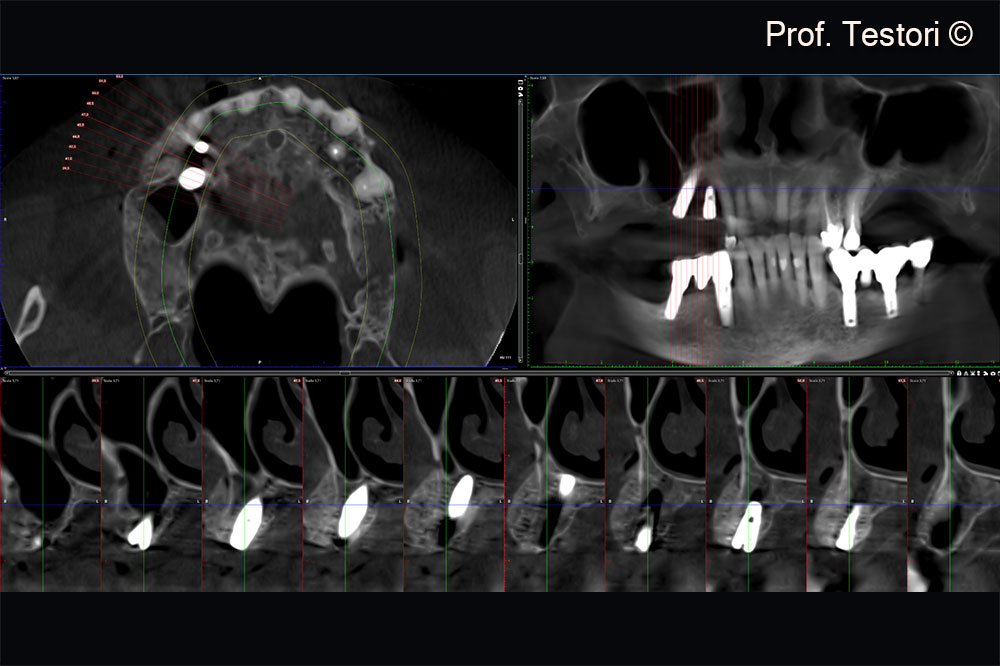

Cone-beam computerized tomography exam after 4 months of healing.